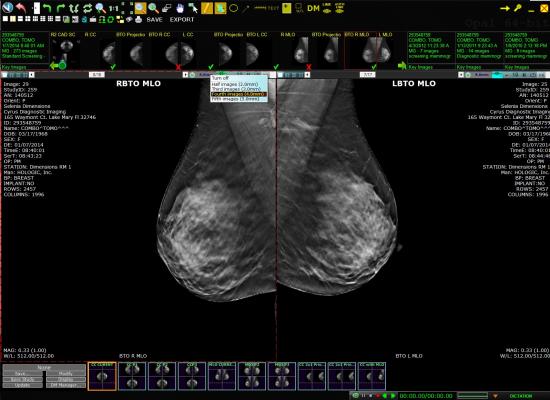

Exa also supports the center’s reading and reporting of digital breast tomosynthesis (DBT), eliminating the need for a dedicated breast imaging workstation. Additionally, the facility uses Exa for viewing and managing echocardiograms for cardiac imaging via the solution’s diagnostic-quality zero footprint universal viewer. In addition to DICOM studies, the vendor neutral archive (VNA) also stores non-DICOM data such as cardiac and holter monitoring data. Exa is structured to support the addition of new facilities and imaging modalities.

According to DeVries, the center purchased a DBT system after installing Exa and was able to avoid the additional expense of a dedicated breast imaging workstation by utilizing the Exa Mammo Universal Viewer with the new imaging system. Through Server-Side Rendering technology, Exa provides quick access to prior exams and large files without the need for prefetching and cyber security with no data transferred to or stored on local workstations.

“We are able to access all studies from any location or workstation with the Exa Universal Viewer, helping enhance efficiency and report turn-around-times so our referring physicians and specialists can deliver the highest quality patient care,” said James Selis, M.D., a diagnostic radiologist at Envision Diagnostic Center. “Since the solution can handle breast imaging and cardiac studies, we have reduced our reliance on dedicated workstations, which lowers our overall costs but as importantly further enhances radiologists’ productivity and reporting.”